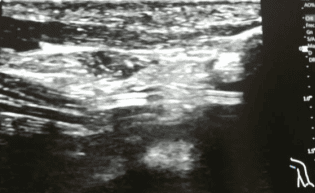

¿Cómo diferenciar el vaso arterial del vaso venoso ecográficamente en el paciente neonatal?